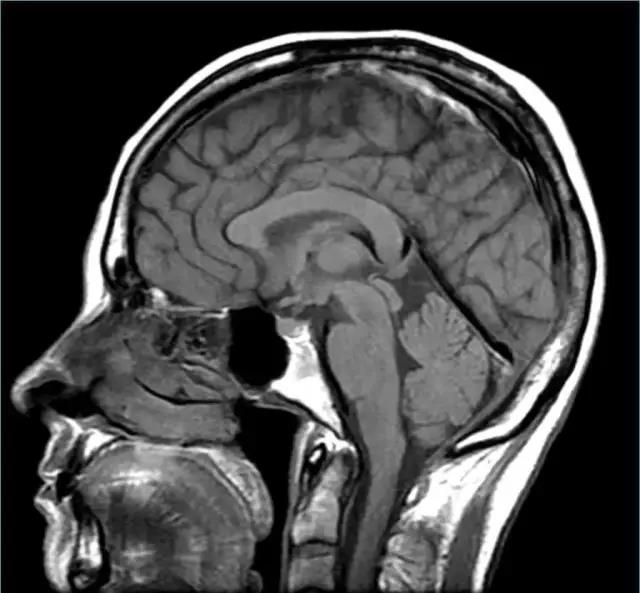

fMRI使用MRI 磁共振成像技術(shù)。 MRI在20世紀70年代發(fā)明,是基于X射線的CAT掃描的演變。 MRI不是使用X射線,而是使用磁場(以及無線電波和其他信號)來產(chǎn)生人體和腦的圖像。

而這一整套的橫截面,讓您穿過頭去看到里面。

fMRI 使用MRI 技術(shù)來跟蹤變化的血流量。為什么?因為當大腦區(qū)域變得更加活躍,他們使用更多的能量,所以他們需要更多的氧氣,使血流增加該區(qū)域的氧氣供應(yīng)。

fMRI的有很多醫(yī)療用途,其最大的缺點是分辨率。

fMRI 成像體素的尺寸不斷縮小,隨著技術(shù)有所改善,使空間分辨率可達立方毫米。大腦有大約1200000毫米體積,所以fMRI 成像掃描將大腦劃分約一百萬小立方體。問題是,對神經(jīng)元的規(guī)模來說,這仍然是相當巨大的,每一個像素包含的神經(jīng)元數(shù)以萬計。更大的問題是時間分辨率,fMRI跟蹤血流,既不精確,且有延遲。